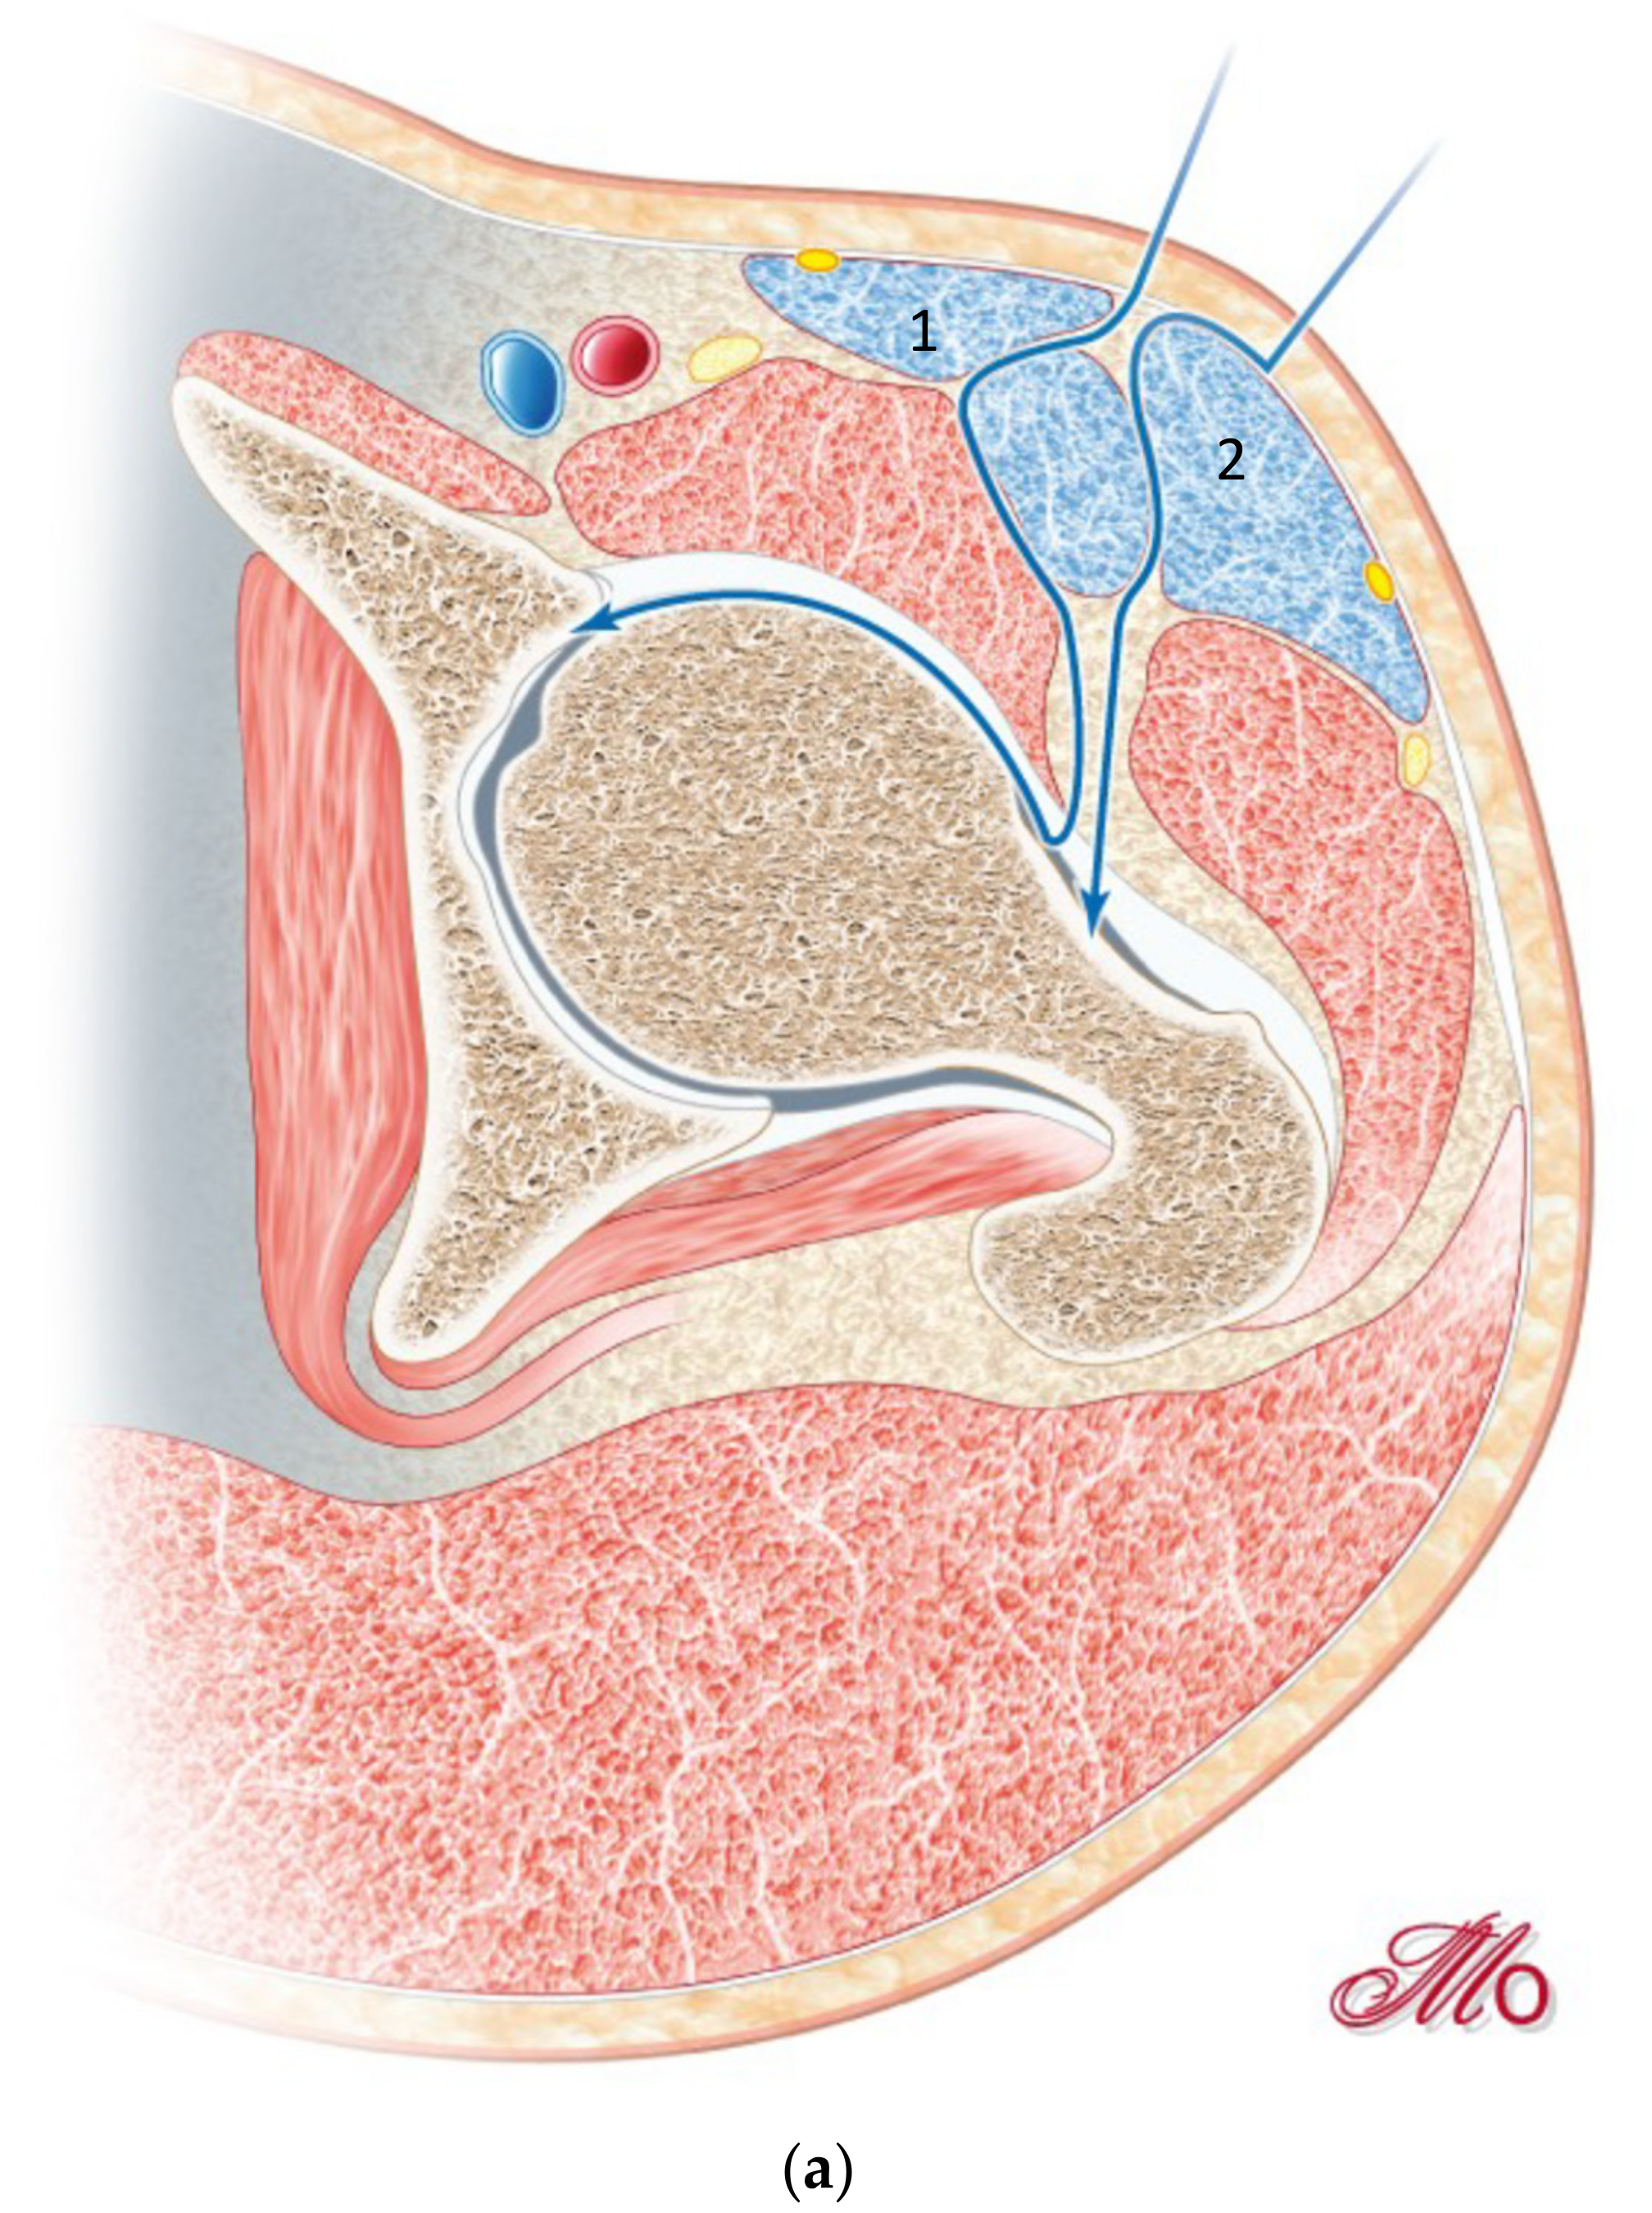

2.3. Surgical Technique